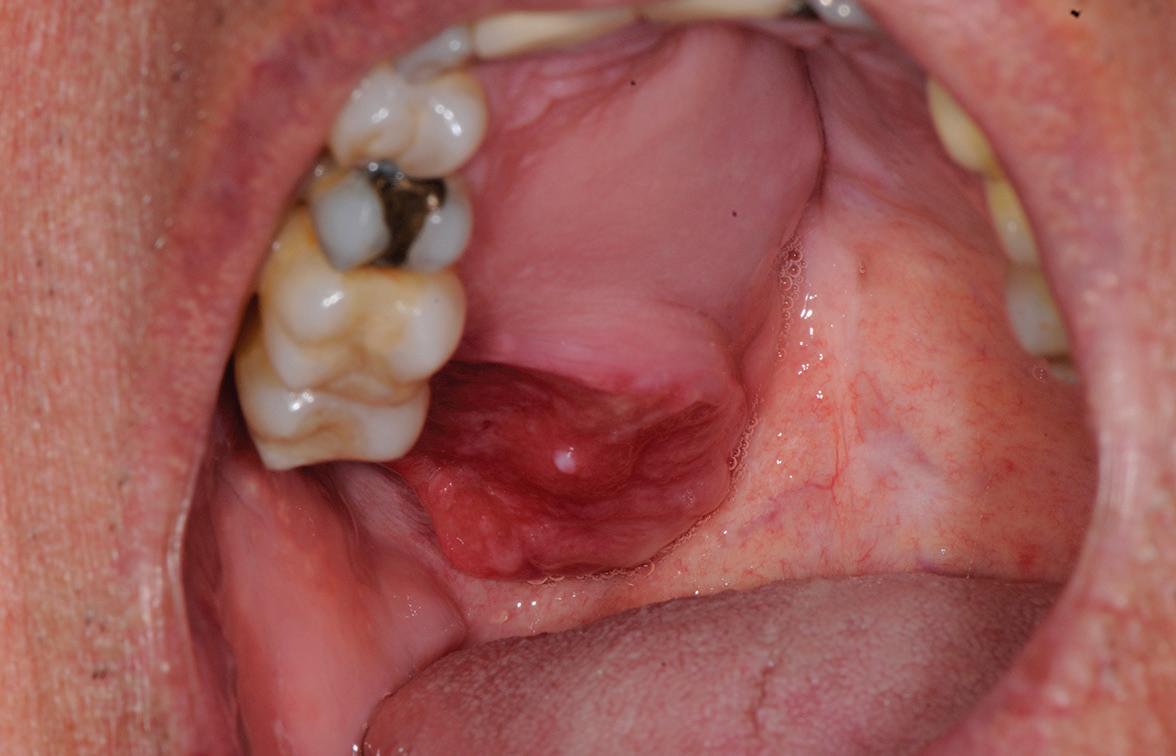

54 Oral Medicine, Oral Diagnosis, Oral Pathology

An unusual clinical and histopathologic presentation of a maxillofacial ameloblastoma: a literature review and case report

Pallavi Parashar

Clayton Davis